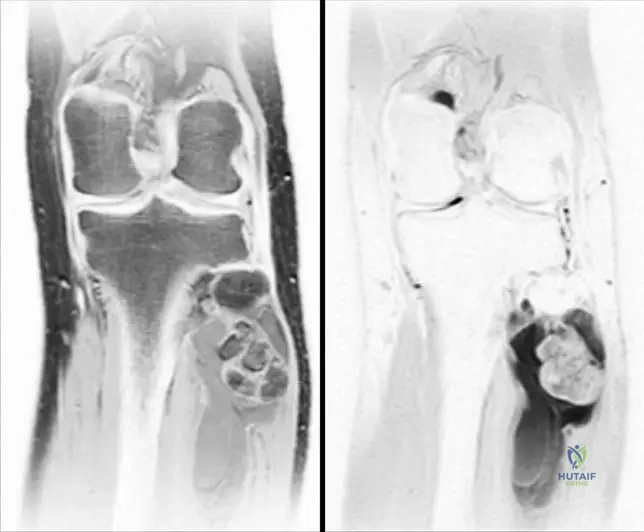

A 16-year-old male presents with chronic knee pain that has been present for several years. Physical examination reveals tenderness around the knee. Radiographs show a lytic lesion in the proximal tibial epiphysis. An MRI confirms an epiphyseal lesion.

View Answer & Explanation

Correct Answer: C

Rationale: Chondroblastoma is a benign cartilage-producing tumor typically found in the epiphysis or apophysis of adolescents or young adults, often presenting with chronic pain. The age (16-year-old) and epiphyseal location are classic for chondroblastoma. Main Distractor: Giant Cell Tumor (GCT) typically occurs in a slightly older age group (20-40s) and usually involves the epiphysis after physeal closure, although it can cross the physis.

Question 54

A 16-year-old male presents with chronic knee pain. Radiographs reveal a lytic lesion in the proximal tibial epiphysis. An MRI confirms an epiphyseal lesion. The patient's pain has been present for an extended period.

Correct Answer: B

Rationale: The clinical context states that matrix calcifications are present in approximately one-quarter of chondroblastomas, making this a characteristic radiographic feature, though not universally present. Main Distractor: A sclerotic rim can be seen in some benign lesions, but matrix calcifications are specifically highlighted for chondroblastoma.

Question 57

A 16-year-old male presents with several years of knee pain. Physical examination reveals tenderness around the knee joint and mild regional muscle atrophy. Radiographs show a lytic lesion in the proximal tibial epiphysis.

Correct Answer: D

Rationale: The text explicitly states that "Pain is the most common clinical finding" for chondroblastoma, and it "may be present for many years before diagnosis." Tenderness, regional muscle atrophy, and antalgic gait are also mentioned. Main Distractor: Acute onset of pain is incorrect, as the pain is typically chronic and long-standing.

Question 58

A 16-year-old male presents with knee pain. Imaging reveals a lytic lesion located in the epiphysis of the proximal tibia. The patient has open growth plates.

Rationale: The text states that chondroblastomas "occur in primary or secondary ossification centers" and are "usually localized to the epiphysis or apophysis." Main Distractor: The metaphysis is a common location for many other bone tumors (e.g., osteosarcoma, osteochondroma), but chondroblastoma's predilection for the epiphysis/apophysis is a key diagnostic feature.